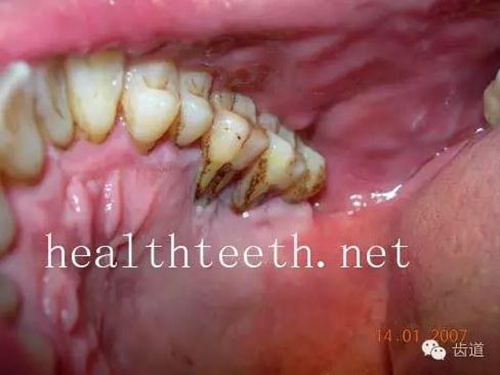

牙周大量牙石堆積